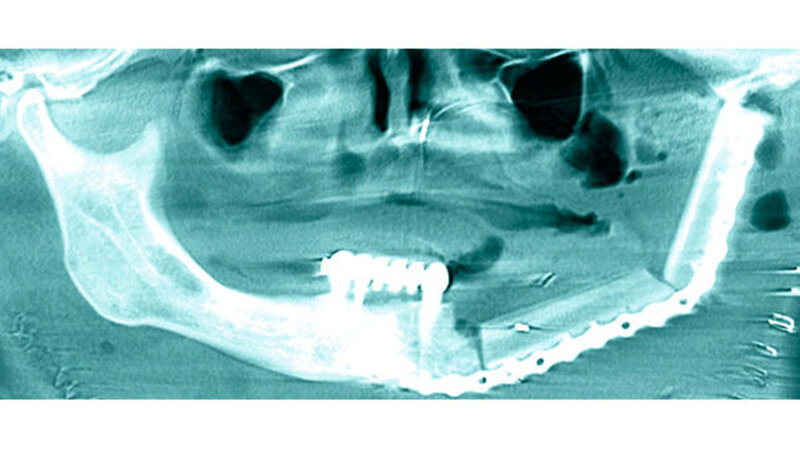

Im Konsens mit dem interdisziplinären Tumorboard wurde die Patientin einer primär chirurgischen Therapie zugeführt mit der Option einer anschließenden Chemotherapie. Bei notwendiger Hemimandibulotomie mit kombiniertem Weichteilverlust wurde eine primäre Rekonstruktion mittels mikrovaskulärem Fibulatransplantat geplant. Die Prozedur wurde nach Evaluation der peripheren Durchblutungssituation der Beine CAD/CAM-geplant durchgeführt (Abbildungen 6 und 7).

Die endgültige histologische Aufbereitung zeigte einen malignen, Osteoid-produzierenden Tumor, der einem Osteosarkom der TNM-Klassifikation pT2b pN0 (0/37) M0 R0 (Abbildung 8) entsprach. Der postoperative Heilungsverlauf verlief komplikationslos, so dass die Patientin nach drei Wochen nach Anbindung an die Hämatologie in die ambulante Nachsorge entlassen werden konnte. Eine Chemotherapie wurde auf Wunsch der Patientin nicht durchgeführt. Die pulmonalen Verdichtungen erwiesen sich in der Nachkontrolle als größenkonstant. Aktuell ist die Patientin in regelmäßiger Nachsorge ohne Anhalt für ein Rezidiv oder eine Metastasierung.